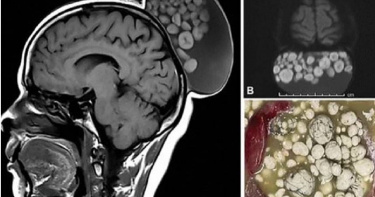

52歲婦女頭長「15公分腫瘤」 醫震驚:像一袋彈珠

印度一名52歲婦女頭長15公分腫瘤,裡面脂肪狀的小球,醫師表示,就像是一袋彈珠。女子說,腫瘤從她小時候開始慢慢生長。據《每日郵報》報導,一名印度住在邦加羅爾的婦女,頭部切除了15公分腫瘤,裡面都是頭髮和脂肪狀小球。女子說,腫瘤從她小時候就有了,而她從來都沒想到要切掉它。醫師在醫學雜誌上公布腫瘤的照片,腫瘤大小不一,就像一袋彈珠。斯里沙迪亞賽高等醫學科學研究所的醫生表示,這種情況不常見。女子手術切除後,醫師發現腫瘤中有脂肪,和頭髮漂浮在液體中,經過檢查後,發現它是表皮囊腫,在醫學上稱為成熟囊性畸胎瘤。據英國國家醫療服務體系(NHS)稱,表皮囊腫是非癌性的,由胚胎細胞發育而來,有毛髮、液體、牙齒等,這意味細胞可能會變成多種組織類型。報導稱,目前不清楚女子症狀發生原因。醫師說,成熟的囊性畸胎瘤經常出現在頭和頸部。國民醫療服務體系表示,如果囊腫沒有引起任何症狀,患者可能只需要定期掃描檢查就好。醫師說,在腫瘤切除後的6個月內,他們監測了婦女的狀況,腫瘤沒有復發。據了解,表皮囊腫在夏天容易發炎,也有可能是因為吃太多油炸物和刺激性食物,或是熬夜、壓力大等,都可能是發炎原因。